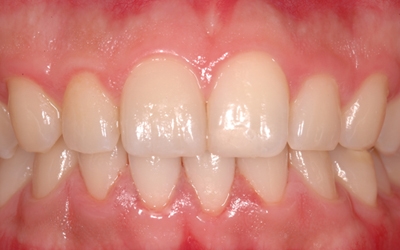

1. 스케일링

잇몸 질환은 플러그가 누적되어 염증으로 발전해 발생되는 것이므로 치석을 제거해주는 스케일링을 정기적으로 받는다면 좋은 잇몸을 유지할 수 있답니다. 스케일링의 경우엔 보험이 적용되기 때문에 1-2만 원 정도의 저렴한 비용으로 받을 수 있기 때문에 필수로 정기적으로 받아보시기 바랍니다.